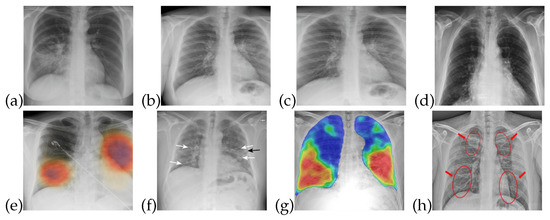

The training data for both healthy and patients infected with COVID-19 are collected from publicly accessible X-ray images [34]. The images obtained are of different sizes and image quality, so that characteristics such as contrast, sharpness, and brightness levels are different for almost all of these images. X-ray images are useful in the diagnosis of some of the rare causes of acute diarrhea. Findings on an X-ray images indicate that organic causes of acute diarrhea include intestinal dilation, irregular mucosal surface, and increased luminal fluid. For the observation of diarrhea, different patterns can be observed in X-ray images. Figure 1 shows that healthy/normal patients and COVID-19 infected patients have different patterns in their respective X-ray images. There are different patterns for recognizing the symptoms of COVID-19 that can be obtained from X-ray image. The detail of these symptoms from an X-ray images is given in [35].

Figure 1.

X-ray images for healthy and COVID-19 infected patients: (a–d) Normal patients X-ray (e–h) COVID-19 infected patients X-ray.

The data utilized in this work are in the form of X-ray images, which are useful for detecting lung and liver infections as well as COVID- 19 [37]. Common features that can be observed through X-ray images are chest pain, diarrhea, and viral pneumonia features [7,34,38]. In the early stages of COVID-19, though, X-ray images do not show any abnormalities related to the virus. However, as the disease progresses, abnormalities related to chest pain, diarrhea, and pneumonia do become noticeable in the X-ray images, as shown in Figure 1. In Figure 1a–d, one can see normal patient X-ray and Figure 1e–h highlights COVID-19 infected patients X-ray.